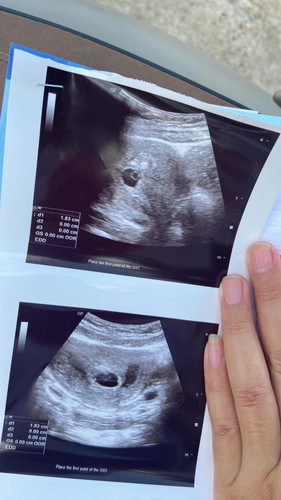

ท้องได้ 7สัปดาห์6วัน อัลตร้าซาวด์ไม่เจอตัวแต่เจอขาวๆวงกลมอยู่ในถุง #แบบนี้จะท้องรมมั้ยคะใครมีประสบการณ์ช่วยบอกที

บ้านนี้ไปฝากตอน 7วีค +4 ก็เจอแต่ถุงตั้งครรภ์กับถุงไข่แดงแบบนี้ค่ะ หมอนัดอีกที 1เดือนตอน 11วีค+4 เจอตัวน้องพร้อมหัวใจน้องค่ะ ตอนนี้ 20วีค+6 ดิ้นเก่งมากค่ะ☺️ อย่าเครียดนะคะน้องกำลังโตค่ะแม่☺️

เค้าเองก็ฝากตอน 7 วีค เจอถุงตั้งครรภ์ กับถุงไข่แดงแบบนี้ค่ะ มาเจอน้องช่วง9-10w ค่ะ ตอนนี้31w+1แล้วค่ะ แม่อย่าเครียดน้าา🥰🥰

ปกติค่ะ ถุงไข่แดง บ้านนี้ 7 วีค เจอแค่ถุง เจอน้องตอน 9 วีค ซาวด์ผ่านช่องคลอดค่ะ